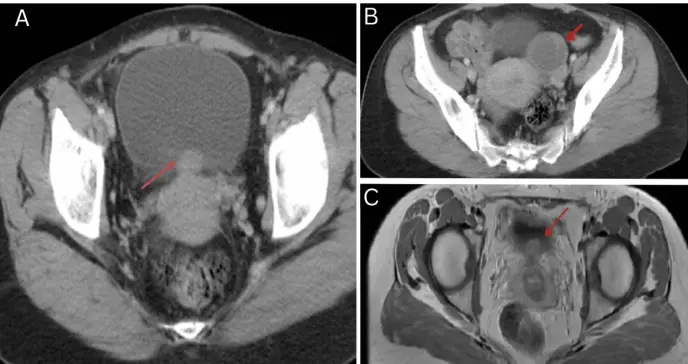

El análisis de orina mostró hematuria macroscópica persistente. La razón internacional normalizada (INR) fue de 2,5, y tanto el hemograma como las pruebas hepáticas y renales resultaron normales. La ecografía reveló una masa en la pared posterior de la vejiga, y una tomografía computarizada confirmó la presencia de una masa de 3 cm con extensión hacia el útero. También se identificó un quiste funcional de 5 cm en el ovario izquierdo.

Para una mejor caracterización de los hallazgos, se solicitó una resonancia magnética pélvica. Las imágenes mostraron un engrosamiento de la pared vesical posterior con múltiples espacios quísticos de alta señal en T2, así como cicatrices compatibles con la cesárea previa y adelgazamiento de la pared uterina. Aunque no se identificaron masas intrauterinas definidas, se observó un engrosamiento en la pared uterina posterior. Los ovarios tenían un tamaño y morfología conservados.

Con base en estos hallazgos, se consideraron múltiples diagnósticos diferenciales: neoplasia vesical, endometriosis vesical, fibroma uterino, sarcoma, o incluso la posibilidad de un cuerpo extraño. Aunque la cistopanedoscopia y la laparoscopia diagnóstica podrían haber ofrecido mayor claridad diagnóstica, se optó por un abordaje quirúrgico directo dada la solidez de la información clínica e imagenológica. El objetivo era reducir intervenciones innecesarias para la paciente.